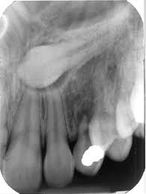

If you come to the clinic with pain at the last molar area, and difficulty in opening your mouth, it is likely that wisdom teeth are impacted under the gums. We will take an x-ray and find out if the impacted wisdom tooth needs to be removed. Sometimes a small cut is enough for the wisdom tooth to come out.

Surgical extraction is the method by which a tooth is removed from its socket, after creating a flap and removing part of the bone that surrounds